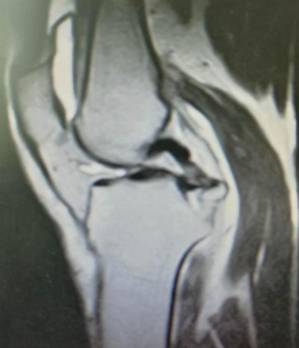

手术技术上与国内领先医院接轨,并不断创新。系统开展膝关节骨性关节炎的阶梯治疗方案,早期采用中医中药、理疗、肌力训练等方法;中期采用膝关节周围截骨、单髁置换等手术治疗,充分保留膝关节功能,术后患者康复快。终末期采用膝关节表面置换术治疗。系统开展股骨头无菌性坏死的保头治疗,早期可采用中医中药内服,钻孔减压术治疗,中期可采用髋关节外科脱位技术,充分刮除头内坏死骨,植入新鲜骨质,使坏死股骨头重新获得新生。常规开展复杂的人工髋膝关节置换手术、人工髋膝关节翻修手术。术后采用先进的康复理念和康复方案帮助患者在无痛状态下恢复关节功能。

全膝表面置换术治疗重度骨关节病

优点:疗效可靠,膝关节病的最终解决方案。

单髁置换术治疗单间室骨关节病

优点:损伤小、康复快、可早期下床。